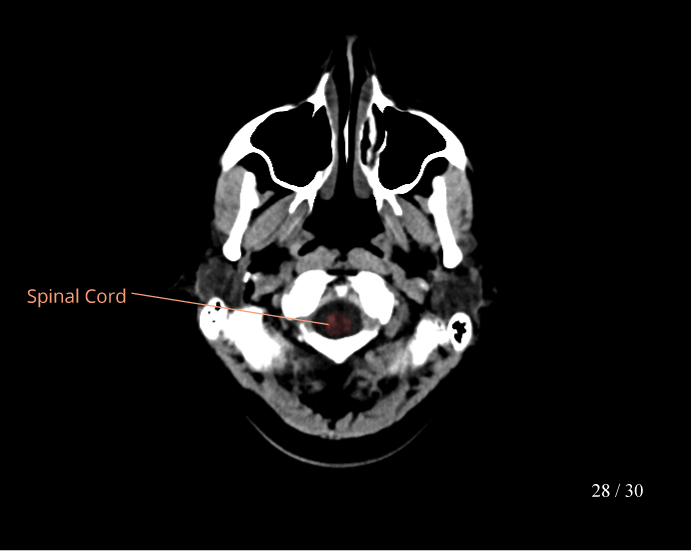

CT Brain Anatomy